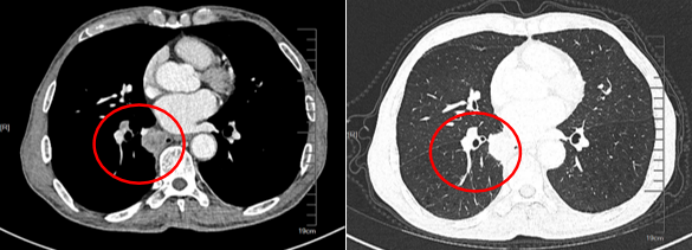

2024年7月21日胸部CT提示:右侧胸腔大量高密度影,中间有较多气体影像,部分肺组织受压不张,支气管胸膜瘘或食管胸膜瘘形成可能(图3)

图片

3  患者胸部CT(2024-07-21)

7月30复查胸部CT提示炎症吸收好转,肺复张较前明显(图4)将抗感染药物降阶梯为头孢哌酮舒巴坦,安置空肠管,启动肠内营养。

4  复查胸部CT(2024-07-30)